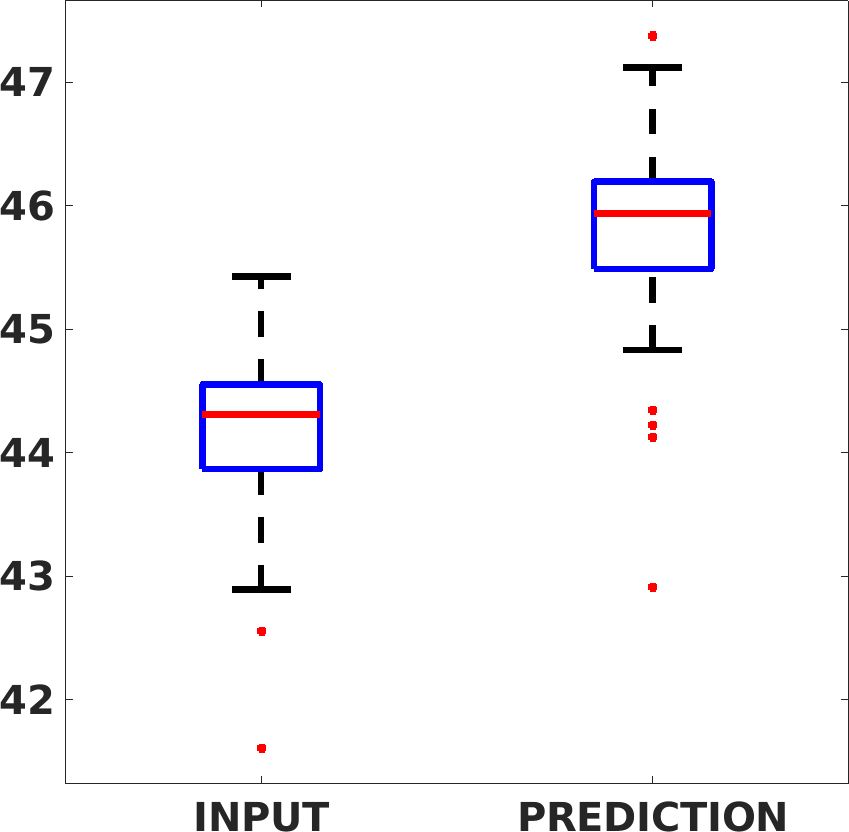

Fig. 8 shows the box plot of the SSIM (a-b-c, left) and MAE (a-b-c, right) quantitative metrics, as performed for PSNR metric. Also, these metrics show that our method improves the results of Cubic convolution both in terms of average value and variability. For example, the SSIM median value improves of on obstetric 4X images and the MAE median value improves of on cardiac 2X images.

Fig. 17 (left) shows the box plot of the quantitative metrics, comparing the target images with the prediction and the Cubic convolution, respectively. The PSNR metric is computed on a data set of 200 images, belonging to the same district, and with the same up-sampling factor. Analysing the obstetric anatomical district and concerning the corresponding raw images (Fig. 7 (a, left)), the denoising allows the network to significantly improve the results of the up-sampling and the prediction. In particular, comparing the target images with the predicted images, the median PSNR value of obstetric 2X denoised images is 51.8, compared to the median PSNR value of obstetric 2X raw images which is 36.9.

Fig. 17 (right) shows the histogram of the absolute value of the error with respect to the target, of the prediction and Cubic convolution respectively. This result shows that our framework increase of and (2X and 4X, respectively) the number of pixels where the prediction error is lower than 5, which is very similar to the target when visually analysing the images, and improved with respect to the learning framework applied to raw images. According to Fig. 18, our method improves the accuracy of Cubic convolution. For example, the SSIM increases of on cardiac 2X and the MAE increases of on abdominal 4X.